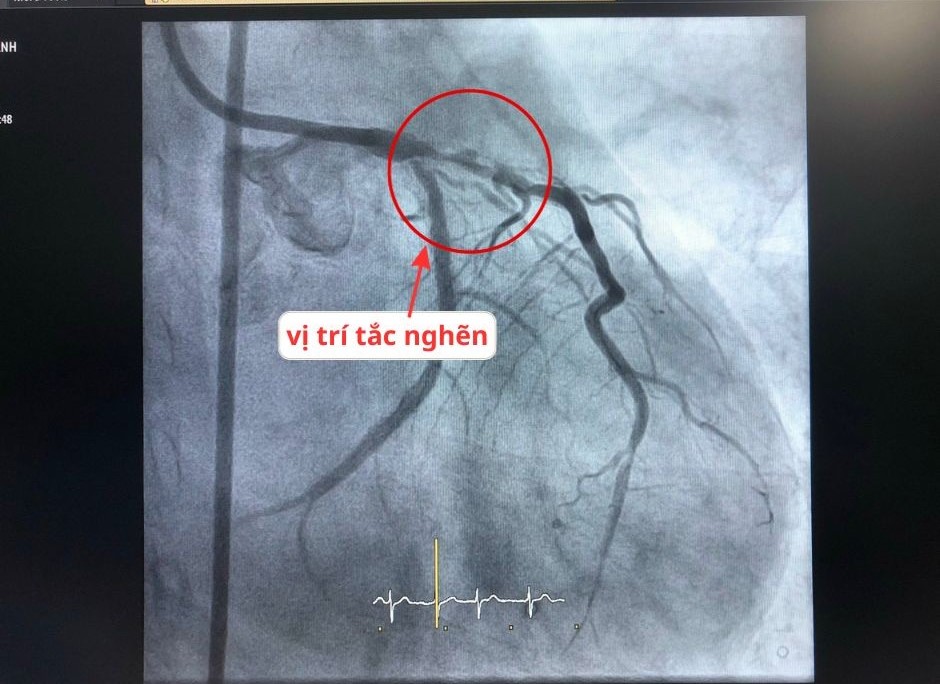

Qua khám bệnh, khai thác tiền sử bệnh, làm xét nghiệm máu, điện tim đồ, siêu âm tim… các bác sĩ nhận định ông có dấu hiệu của cơn nhồi máu cơ tim cấp. Sau khi thực hiện chụp mạch vành, kết quả cho thấy rõ bệnh nhân bị tái hẹp động mạch vành tại vị trí thân chung, đoạn chia nhánh - nơi từng đặt stent trước đây.

width= Hình ảnh động mạch vành bị tắc nghẽn của bệnh nhân

Cụ thể, thân chung hẹp đến 70%, sau đó chia nhánh thì một nhánh đã tái hẹp trong stent cũ tới 99%, một nhánh tái hẹp stent cũ 90%. Bên cạnh đó, thân chung đang phải cấp máu bù cho vùng cơ tim được nuôi bởi động mạch vành phải đã tắc hoàn toàn mạn tính từ lâu.